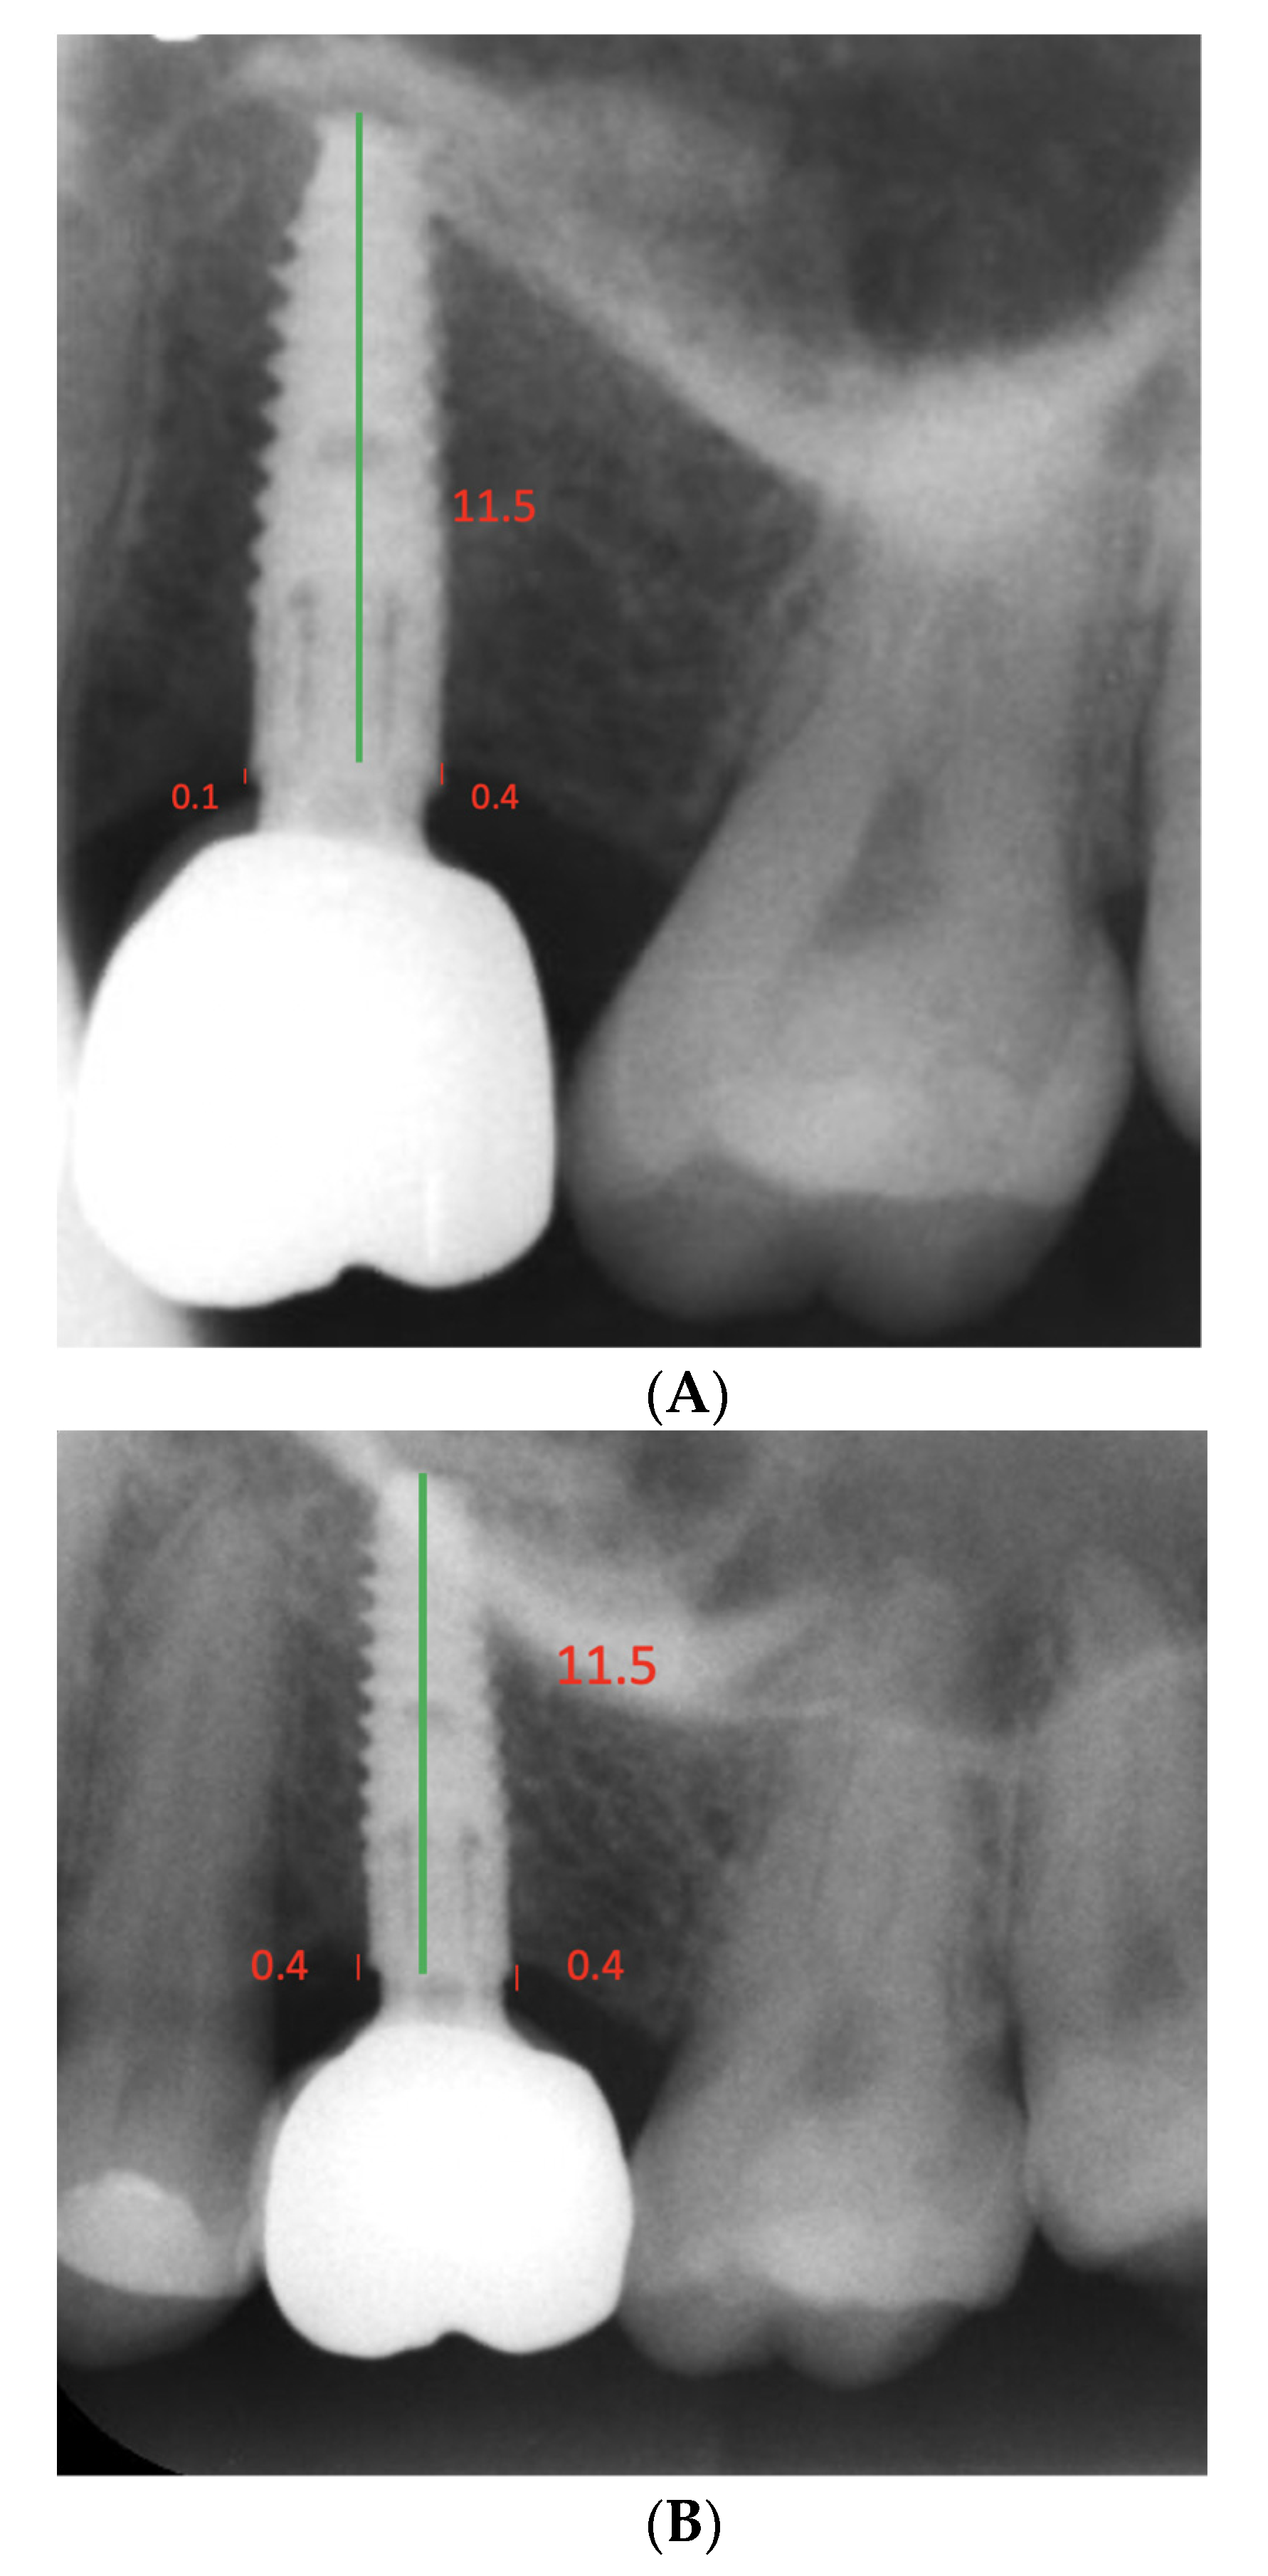

| Bone Levels | Baseline Mean (SD) | Follow-Up Mean (SD) | p-Value |

|---|---|---|---|

| Mesial | 0.45 (0.47) | 0.59 (0.42) | 0.30 |

| Distal | 0.57 (0.69) | 0.78 (0.59) | 0.17 |